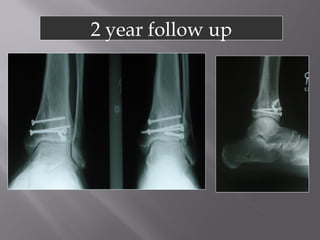

1986 - 24 yo Male

1 year

7 years

14 years

 Works light labor

 Prefers high top boots

 Occasional pain

 Ankle score 80